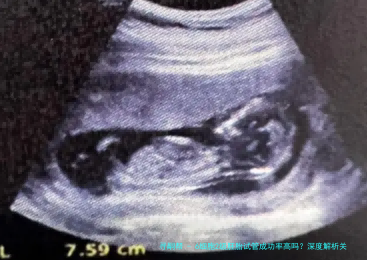

在试管婴儿治疗中,胚胎质量是决计成功率的核心因素。6细胞二级胚胎作为临床多见的中级质量胚胎,实际上际妊娠潜力备受留意。本文将从国际胚胎评介体系体例切入,结合最新临床数据,系统剖析该等级胚胎的着床规则及影响要点。

现行胚胎评估体系体例蕴藏细胞数、破裂均一性和碎片率三大维数。6细胞个体胚胎指受精卵形成后48-72小时形成6个完整细胞体,隶属于发育快慢正常的胚胎。二级评定标准为细胞大小轻度不均,碎片比率在10%-百分之二十五之间。这类胚胎虽非最优等级,但仍具有临床移植代价。

2025年辅助生殖医学同盟数据显示:6细胞2级胚胎的临床怀孕率为38%-百分之四十二,活产率约29%-33%。较优质胚胎减少10-15个百分点,但显著高于4细胞胚胎的怀孕率(百分之十八-百分之二十二)。不同生殖医学中心的实验室水平差异可导致5%-8%的成功率平稳。